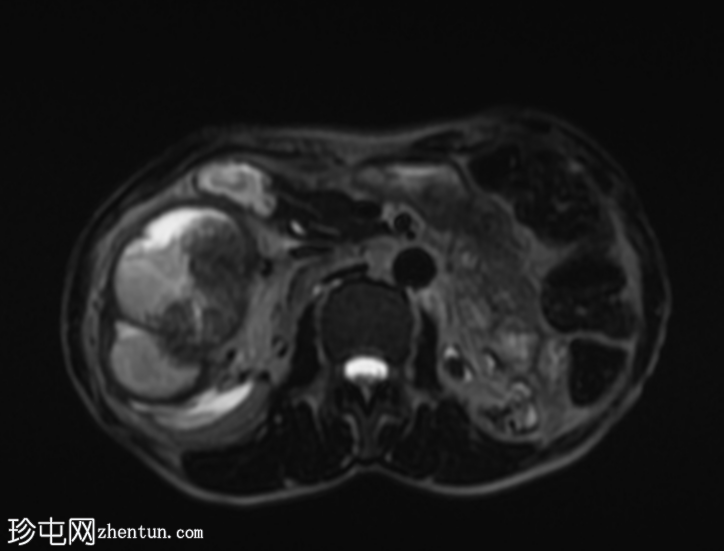

MRI

5.png

轴位

STIR序列

再次观察到上述肾前部外生性病变,其实性成分在T1加权像上呈等高信号,在T2加权像上呈低信号,伴有碎片扩散受限和低ADC值(化脓性物质)。囊性成分内部可见液-碎片/脓液界面。可见内部低信号结石。可见肾周模糊影。该病变压迫并可能侵犯右肾盂,导致中度肾积水。

病灶不规则的低信号,以及液-液界面伴有碎屑(可能为化脓性物质)扩散受限和肾周模糊,再次高度提示炎症性病变(黄色肉芽肿性肾盂肾炎,XGP),而非可能性较小的肿瘤。